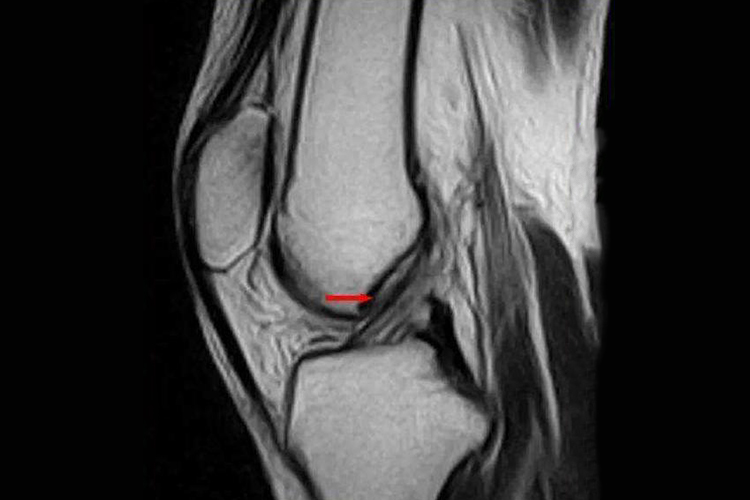

前交叉韧带起自胫骨髁间隆起的前方内侧,与外侧半月板的前角愈着,斜向后上方外侧,纤维呈扇形附着于股骨外侧髁的内侧。正常前交叉韧带在MRI上表现为条状低信号影,韧带连续,无断裂。

前交叉韧带是膝关节的静力性稳定结构,对膝关节的稳定起着至关重要的作用。前交叉韧带断裂后可以产生明显的膝关节不稳,严重影响膝关节的运动功能,随之继发关节软骨、半月板等结构损伤,导致关节退行性变和骨关节炎,若出现不适,需尽快到医院就诊。